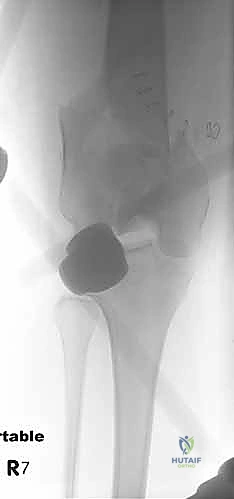

- المفاصل الصناعية (Arthroplasty): في حالات كبار السن حيث يكون الكسر مفتتاً جداً ولا يمكن تثبيته، قد يكون استبدال مفصل الركبة بمفصل صناعي خاص (Tumor/Hinge Prosthesis) هو الحل الجذري والسريع لعودة المريض للمشي فوراً.